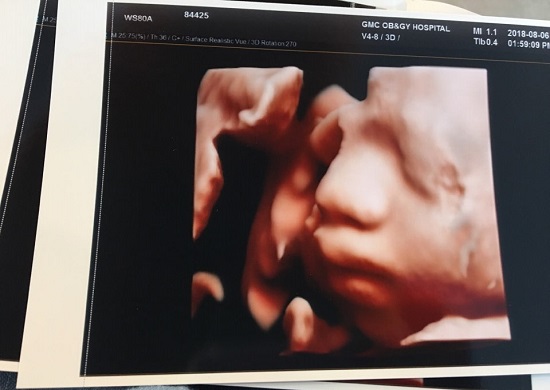

2018년 10월 태어난 조카. 저출산 시대, 아이 낳고 키우기 조금은 더 든든하도록 임신과 출산 지원 정책이 다각도로 검토되고 확대되길 희망한다. |